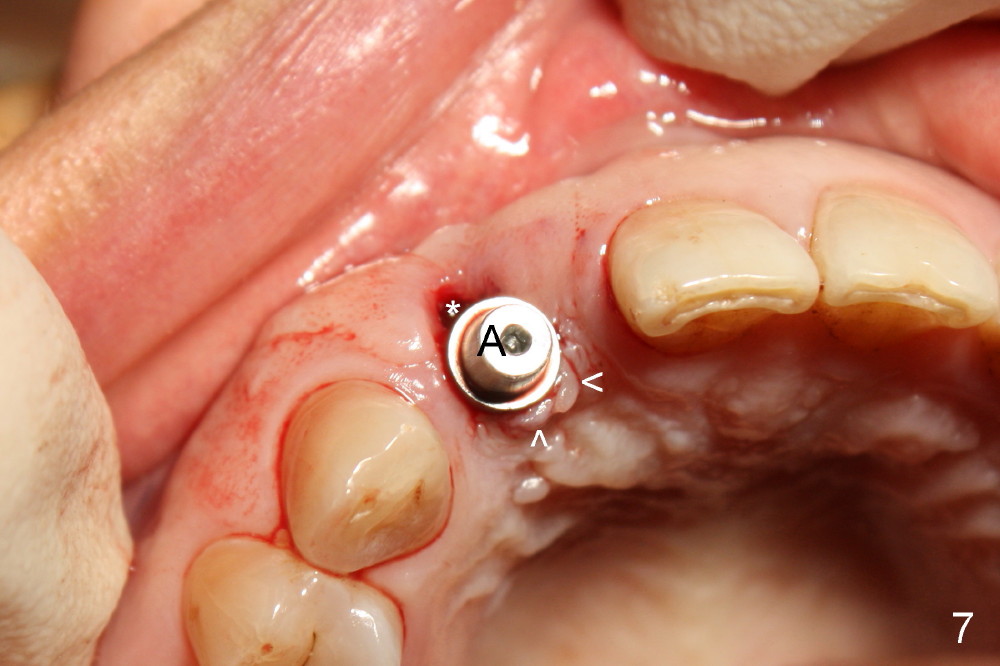

Malpositioned implant in the anterior region is cosmetically unacceptable. Immediate provisional allows us to note the issue immediately. The crown looks too long. Secondly, the provisional is easily dislodged, since the buccal aspect of the angled abutment is over trimmed (Fig.1). The implant (3.8x14 mm), which has been placed 3.5 months, is unexpectedly easily removed by reverse torque (Fig.2). The buccal wall is intact, whereas there seems to be enough bone lingually to place an implant. A small incision is made (Fig.11) so that the gingival tissue can be transferred buccally (Fig.12) and the immediate implant is to be placed palatally (Fig.13 white circle). There is no difficulty forming osteotomy in the palatal wall, followed by inserting 4.5x20 mm tap at the depth of 17 mm (Fig.3,5). But the tap is not palatal enough (Fig.4). By removing more palatal bone, the 4.5x17 implant (Fig.6) appears to be placed palatally enough for restoration (Fig.7; A: abutment; *: buccal gap). The biggest problem is that the palatal flap (Fig.7 arrowheads) cannot be pushed buccally; instead remains palatally. This leads to buccal tissue deficiency (Fig.8). Connective tissue graft is offered, but declined. The patient insists that she has low smile line. Following immediate provisional, mixture of allograft and synthetic graft is placed in the buccal gap (Fig.9). The overbuilt graft is held in place by perio dressing.